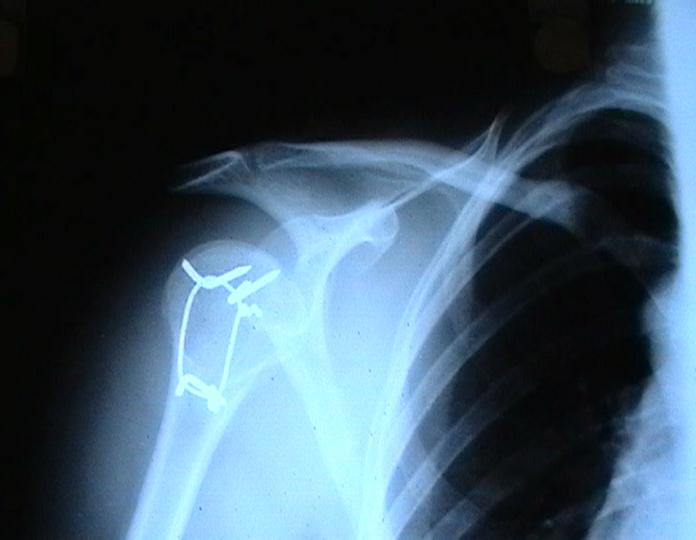

Re: Некроз головки плеча?

Согласен с вашим мнением -асептический некроз головки плеча. Есть ли у вас надежды на реваскуляризацию головки ? Если надеетесь, то имеет смысл продолжать физио, если нет, то следует думать опротезировании.

Переломовывих плеча сложная проблема и технически не уверен как для коллег, но для меня сколько я не встречался, технически сложно *вытянуть* вывихнутую головку из-под впадины. Последнее время не применяю пластины для фиксации перелома, а использую спицы и проволочную петлю (тем более часто и густо спонгиозные винты не держатся в головке прочно).